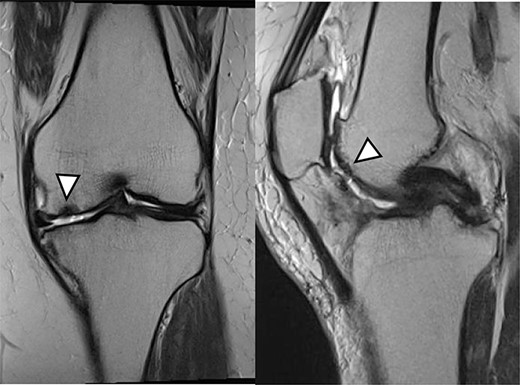

MRI findings at 1 year after the surgery indicated signal intensity area in the grafted area for the patient with JACC (Fig. 8), whereas the patient who underwent Reveille CP exhibited greater thickness at the grafted area as compared to the surrounding healthy cartilage (Fig. 9). The MOCART score at 1 year after the Reveille CP surgery (60 points) was higher than that of JACC (50 points).

One year after Reveille CP. The graft area was thicker than surrounding healthy cartilage (arrowhead).

Five years after JACC. MRI showed the graft area was thicker than the surrounding healthy cartilage (arrowhead).